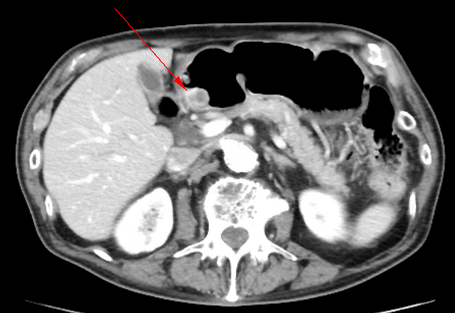

• CT検査

消化管間質腫瘍(Gastrointestinal stromal tumor:GIST)は、固有筋層に発生する粘膜下腫瘍の一種です。頻度としては10万人に1〜2人と稀な腫瘍で、本邦においては胃に多い(胃→小腸→大腸、食道の順)と言われています。男女差はなく、中高年に多い傾向があります。